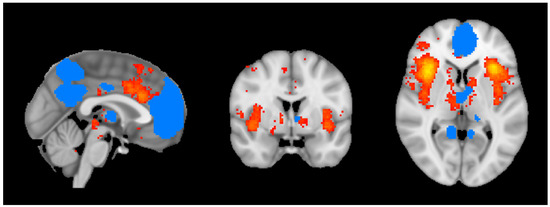

2.6. Insula–DMN Functional Connectivity

Figure 1. Illustration of selected ROIs for resting state functional analysis, including the insula (in red) and DMN (in blue) for the template subject. ROIs are shown in axial (right image), coronal (center image), and sagittal (left image) planes in neurological convention.